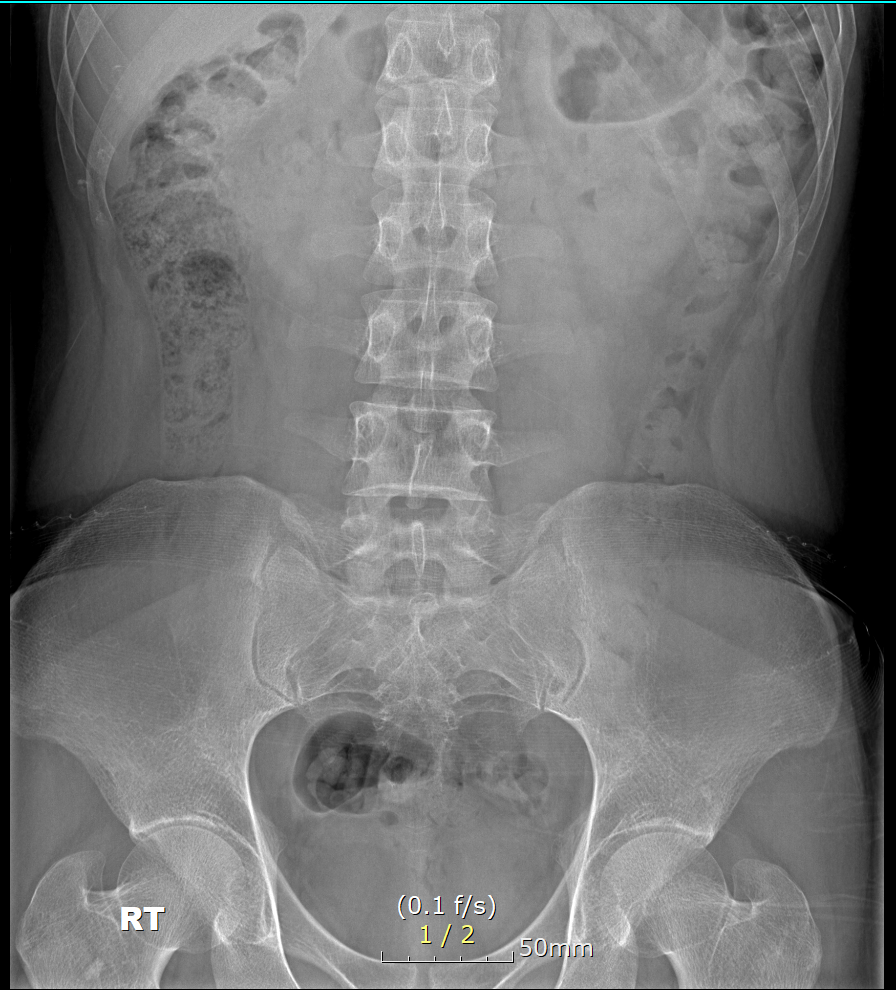

제 허리골반 통증의 이유가 무었일까요?

23년9월경 통증이 시작되었고,,, 디스크 증상 의심받아 약물치료 주사치료(신경주사)

< mbb , epidural >약 5회 , 체외 충격파 , 로컬에서 치료받고

대학병원 신경외과, 정형외과 들러 진료 받으니 디스크로 아프건 아닌거 같다고 들어 결국 아픈 이유를 못찾았습니다.. ct mr 검사 결과 정상적인 허리라고 들었습니다.

- 현재 허리는 뻐근하며 골반윗쪽 누르면 통증이 있고 허리도 누르면 통증이 있습니다.

허리아래 양쪽 윗엉덩이라고 해야할지 애매하네요 .,,,

mri 판독 결과 남깁니다..

Clinical information: back pain

Pulse sequences

- T2WI and T1WI sagittal, T2WI and T1WI axial

- T2WI fat suppression sagittal

- T2WI coronal

- T2WI whole spine sagittal image

- contrast: (-)

T12-L1 level에서 disc가 뒤쪽 Lt. central aspect로 protrusion되어 있고 mild한 dural sac indentation을 주고 있음.

그 외 disc level과 neural foramen에서 definite한 abnormality는 보이지 않음.

Vertebral body의 SI, shape, 그리고 alignment도 정상이며, scanned TL-spinal cord내에 definite한 abnormal signal intensity는 보이지 않음.

• 1번 째 사진